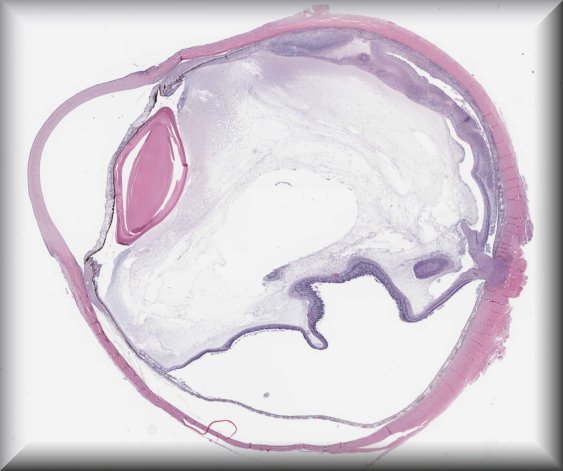

Julia Weller (Erlangen, Germany): Diffuse choroidal hemangioma, intraocular ossification, secondary angle closure glaucoma in a young female patient with Sturge-Weber syndrome. |